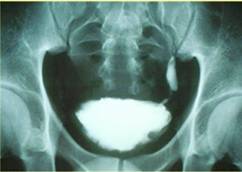

Bệnh sán máng (Schistosomiasis)

-Phần lớn hay gặp dân nhập cư từ châu Phi và một số ít ở châu Á, các loại sán máng hay gặp là S.mansoni, S.intercalatum, S.japonicum, S.haematobium.

-Khi sán máng sống hoặc ký sinh trong nhu mô cơ quan gan hoặc ruột sẽ gây nên các triệu chứng tiêu chảy, gan lớn, tăng áp tĩnh mạch cửa, ấu trùng di chuyển lạc chỗ đến hệ thần kinh trưng ương. Nếu sán máng ký sinh và gây bệnh ở đường tiết niệu sẽ gây các triệu chứng tiểu máu, thận ứ nước, dò cơ quan, vô sinh,…

-Chẩn đoán các bệnh này chủ yếu là làm thế nào phát hiện trứng sán trong phân hoặc trong nước tiểu. Xét nghiệm huyết thanh học có giá trị.

-Điều trị với thuốc đặc hiệu là Praziquantel